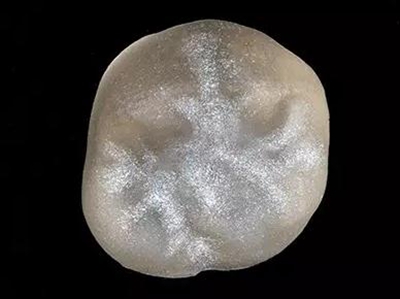

16牙位牙齒牙合面觀.

牙齒經過根管治療且充填修補,需要重新修復。